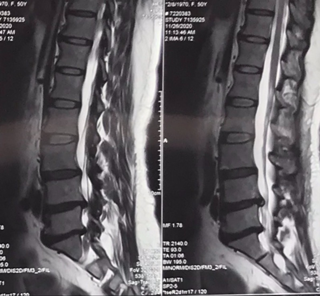

患者腰椎X片及MRI